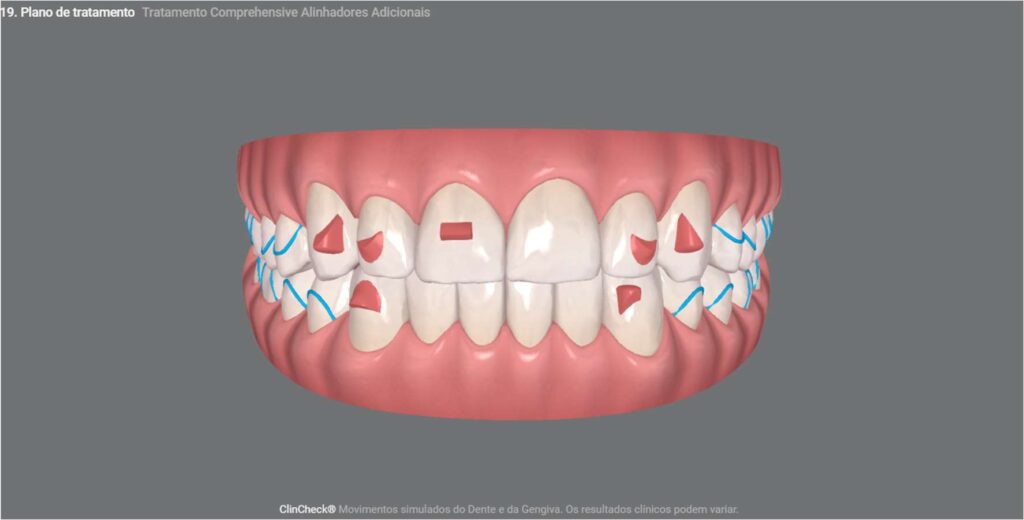

No primeiro ClinCheck deste paciente, apresentamos a fase inicial do planejamento, que visava o alinhamento, nivelamento e aprimoramento estético dos dentes anteriores. Se tivéssemos seguido apenas o que ele desejava, teríamos encerrado o processo ao final dos 20 alinhadores propostos nessa fase. No entanto, conscientes de que poderíamos oferecer mais, elaboramos o segundo ClinCheck para aprimorar ainda mais o tratamento, distribuindo melhor a carga mastigatória e aprimorando o encaixe da mordida, com mais 20 alinhadores.

Para concluir e assegurar um tratamento de alta qualidade à altura do produto Invisalign, realizamos o refinamento desse tratamento com mais 13 alinhadores, garantindo que os dentes intercuspidem da melhor maneira possível.

Depois